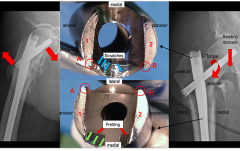

Failure Analysis

Failure Analysis of Implants and Components

We study and determine the mode of failure of explanted implants using a range of specifically designed tests. The large database of information from previously analyzed implant revisions allow us for a more rapid and precise identification of the reasons for any subsequent revisions.

What we offer

- Macro and microscopic analysis of implant surfaces;

- Image analysis of in/ongrowth surfaces (LM, SEM);

- Fractography of structural failures (SEM);

- X-Ray investigative techniques (XPS, EDS);

- Wear assessment of bearing interfaces (CMM, Profilometer combined with a 3-D image software, Wear Scar Mapping);

- Corrosion Assessment (SEM, EDS, XPS).